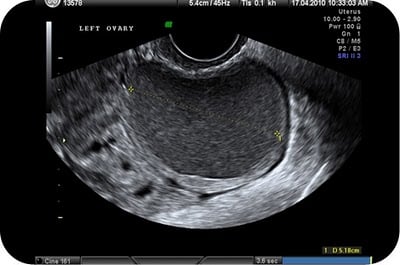

سونوگرافى واژينال

سونوگرافى اولين و ساده ترين روش براى شناسايى کيست است. آندومتريوما معمولاً در سونوگرافى ظاهرى يکنواخت و تيره دارد.